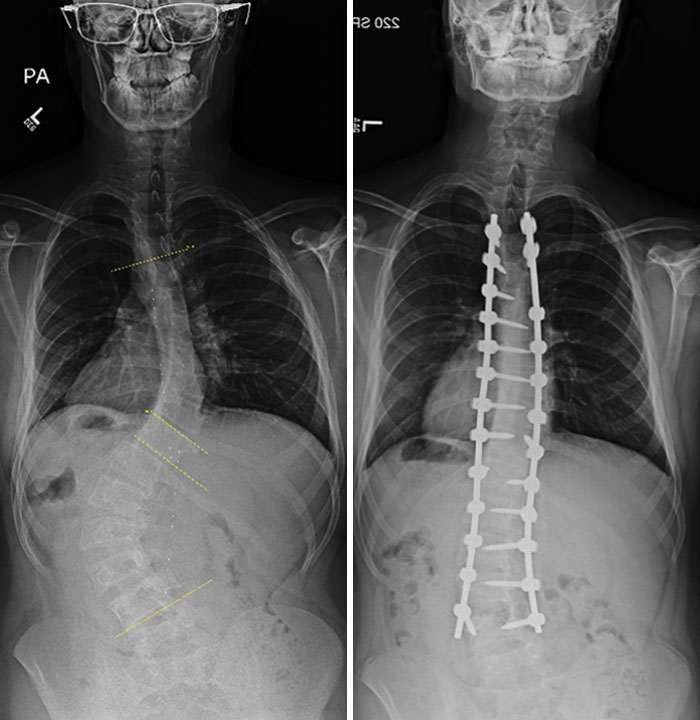

Исправление сколиоза, до и после